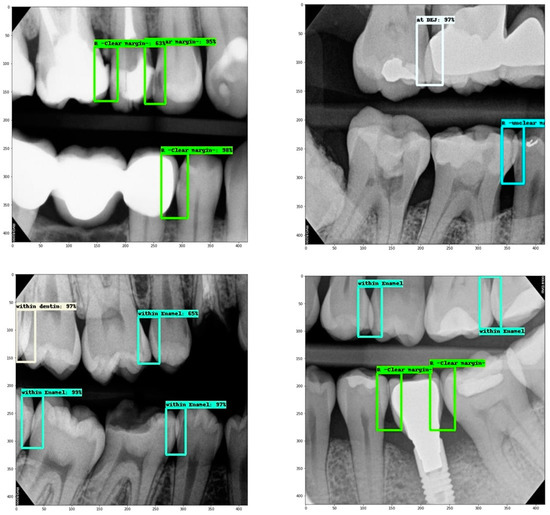

- Overlap within enamel.

- Overlap within a restoration (clear margin).

- Overlap at DEJ.

- Overlap within dentin.

- Overlap within a restoration (unclear margin).